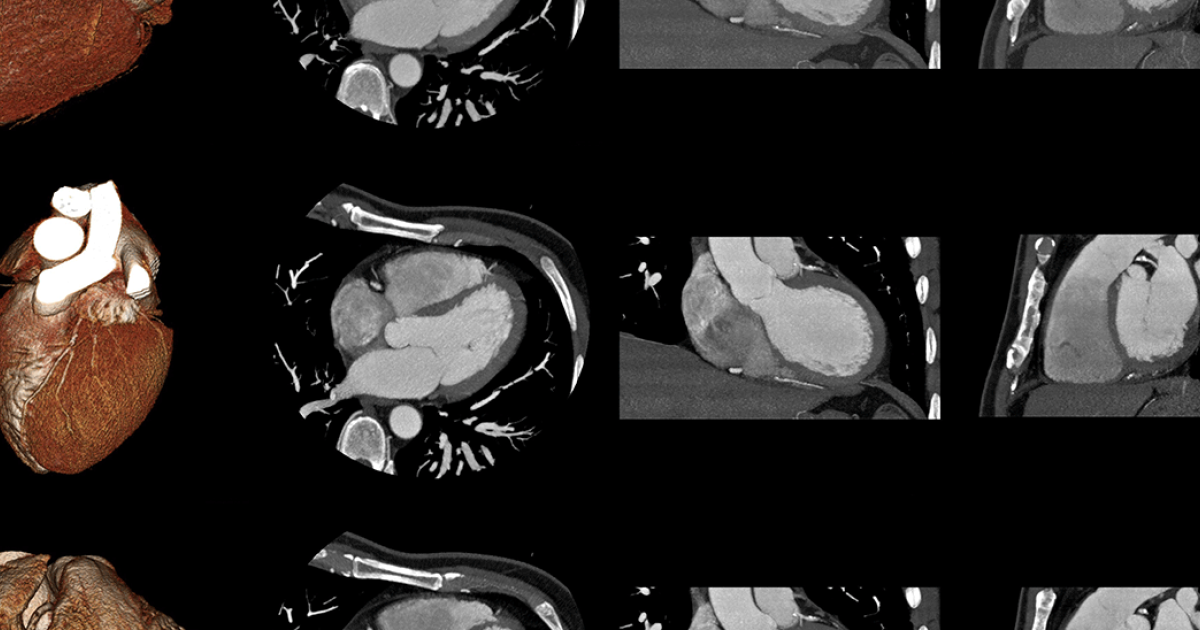

Na maioria das vezes, o paciente é encaminhado a um cardiologista, especialista em doenças do coração. Esse profissional aprofunda a avaliação e solicita exames complementares, sendo o principal deles o ecocardiograma, que é uma espécie de “ultrassom do coração” capaz de mostrar em tempo real o movimento das valvas, o fluxo sanguíneo e o tamanho e função das câmaras cardíacas.

O ecocardiograma pode ser feito via transtorácica (com o transdutor apoiado no peito) ou via transesofágica (com o aparelho introduzido no esôfago para imagens mais detalhadas). Esse exame é essencial tanto para confirmar o diagnóstico quanto para medir a gravidade da estenose ou da regurgitação, avaliar o impacto sobre o músculo cardíaco e orientar a escolha do tratamento.

Outros exames também podem ser úteis em casos selecionados, como o eletrocardiograma simples ou de esforço, que ajuda a identificar arritmias e avaliar a resposta do coração à atividade física; exames de imagem avançados, como a ressonância magnética cardíaca, que permitem analisar com grande precisão a anatomia das válvulas e o grau de regurgitação; e a cateterização cardíaca, que mede pressões dentro do coração e pode ser indicada na avaliação pré-cirúrgica ou em situações complexas.